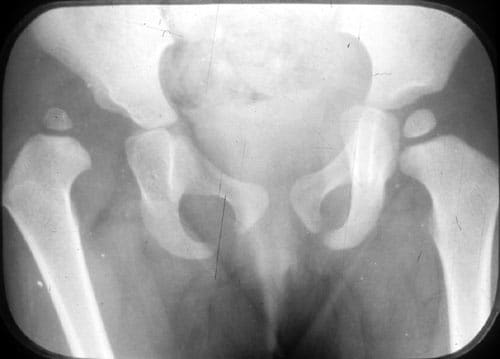

Dr. Pradeep Kumar, with expertise in joint replacement and musculoskeletal oncology extended to pediatrics, manages common conditions like clubfoot (Ponseti casting), developmental dysplasia of the hip (Pavlik harness), scoliosis (bracing or fusion), limb length discrepancies (epiphysiodesis or lengthening), cerebral palsy gait abnormalities, and pediatric fractures/tumors.